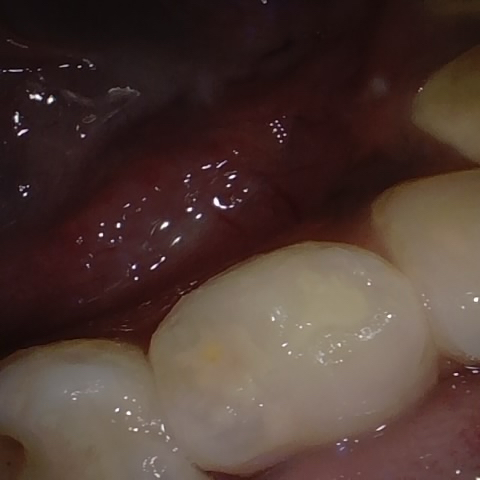

Annotated as "Good"